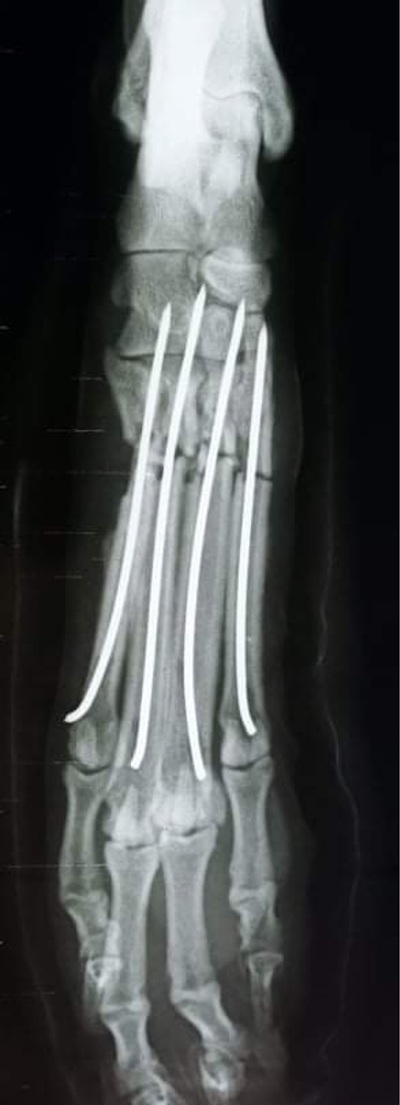

Mittelfußfraktur - OP am 22.11.2021

BRADLEY hat die OP gut überstanden und hat am 03. Dezember 2021 die Klinik verlassen können und ist bis zum Transport am 11. Dezember 2021 auf einer französischen Pflegestelle.